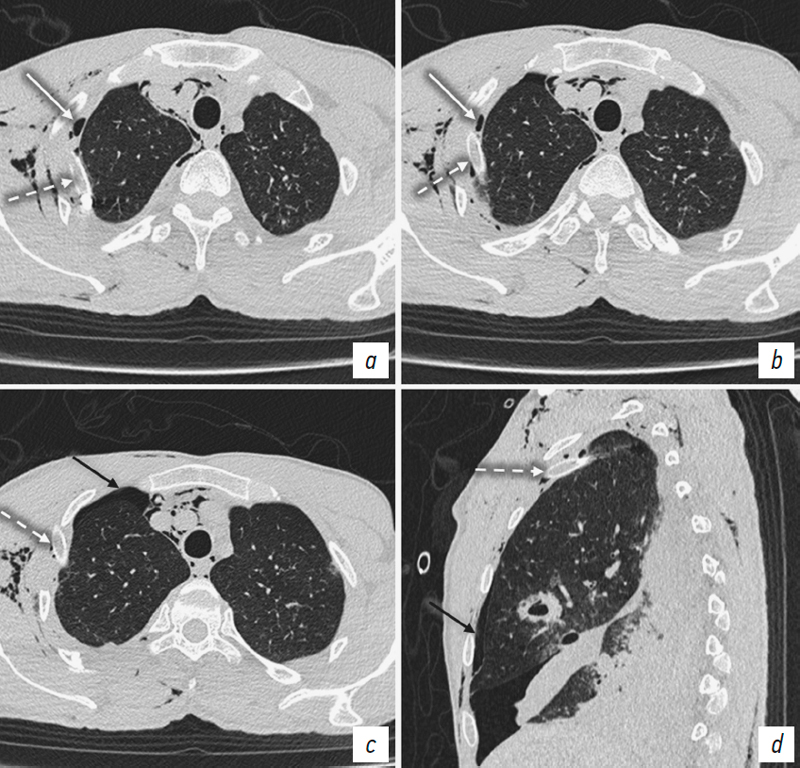

Furthermore, unilateral coexistence of pneumothorax and EPS emphysema was observed in five patients (Fig. 6). In three of these patients, the drainage tube was positioned in the EPS, which resulted in failure to drain the pleural cavity, progressive clinical deterioration, and the development of subcutaneous emphysema (Fig. 7). In one case, severe EPS emphysema was associated with respiratory failure (Fig. 8). US revealed findings characteristic of pneumothorax, including the absence of pleural sliding (Fig. 9).

Fig. 7. Patient T. Chest CT: a–c, axial plane at different levels in the craniocaudal direction; d, sagittal plane through the right hemithorax. Right-sided pneumothorax (black arrows). Pneumomediastinum. Extrapleural emphysema on the right side (white arrows) with a chest drain tube (dashed arrows).

Рис. 7. Пациент Т. КТ органов груди: а–c — аксиальная плоскость на разных уровнях в краниокаудальном направлении; d — сагиттальная плоскость, правый гемиторакс. Правосторонний пневмоторакс (черные стрелки). Пневмомедиастинум. Эмфизема ЭПП справа (белые стрелки) с дренажной трубкой (пунктирные стрелки).